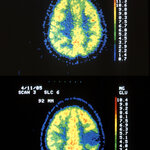

Alda-1 Repairs Defective Alcohol Metabolism Enzyme

A molecule called Alda-1 can repair Aldehyde dehydrogenase 2 (ALDH2), an often defective alcohol metabolism enzyme that affects an estimated 1 billion people worldwide, according to research published Jan. 10 in the advance online edition of Nature Structural and Molecular Biology. The findings suggest the possibility of a treatment to reduce the health problems associated with the enzyme defect. After alcohol is consumed, it is metabolized into acetaldehyde, a toxic chemical that causes DNA damage.  Aldehyde dehydrogenase 2 (ALDH2) is the main enzyme responsible for breaking down…